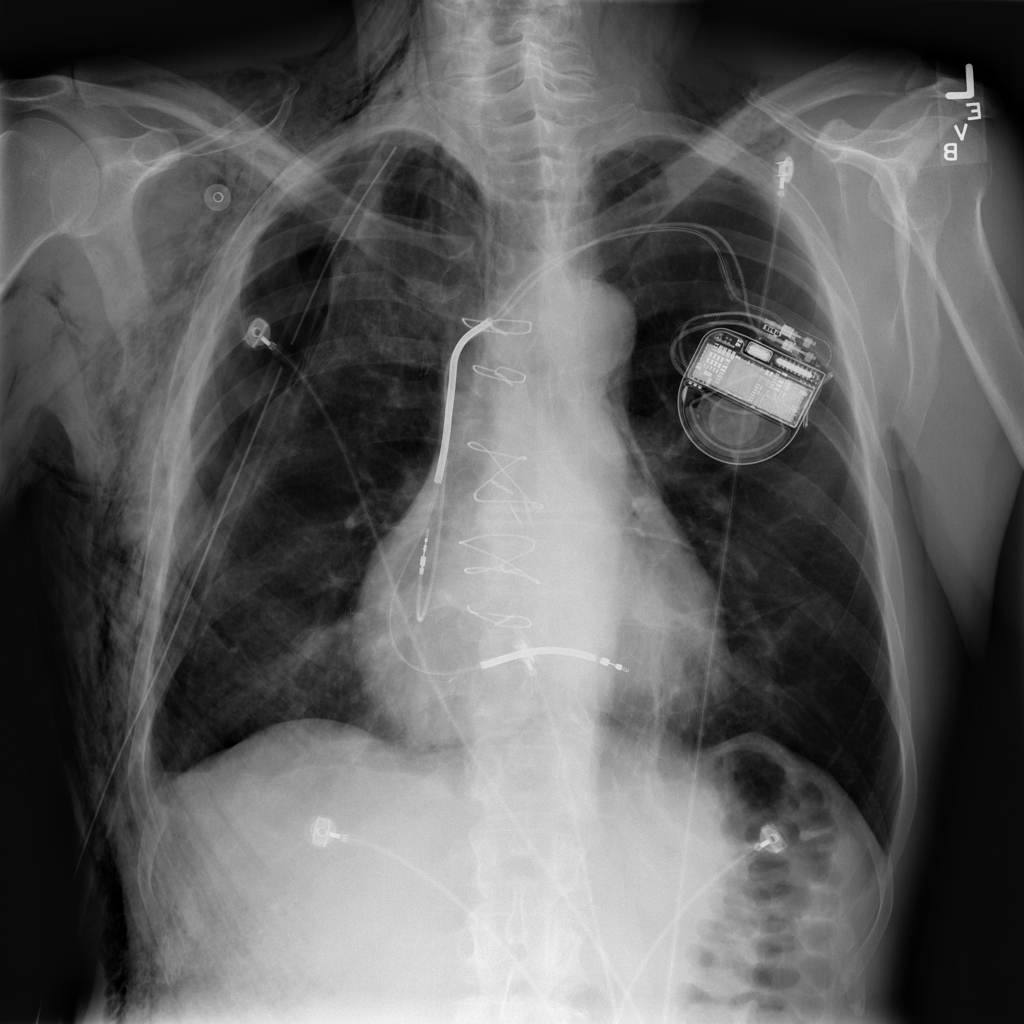

PAT-4639 · IMG-012Pneumothorax

PAT-4639 · IMG-012

AP